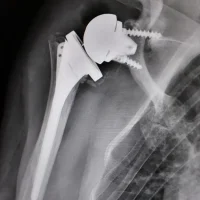

Pour son bon fonctionnement, l’épaule nécessite l’intégrité des surfaces osseuses mais également une bonne fonction du muscle deltoïde (qui donne le galbe de l’épaule) et des muscles de la coiffe des rotateurs qui s’attachent sur les tubérosités de l’humérus. La mise en place d’une prothèse d’épaule peut être nécessaire en cas d’usure importante du cartilage (arthrose), en cas de fracture...